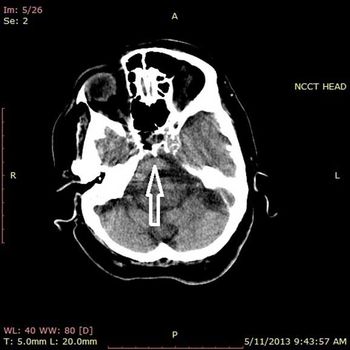

Case History: 24-year-old presents with complaints of headache and seizures.